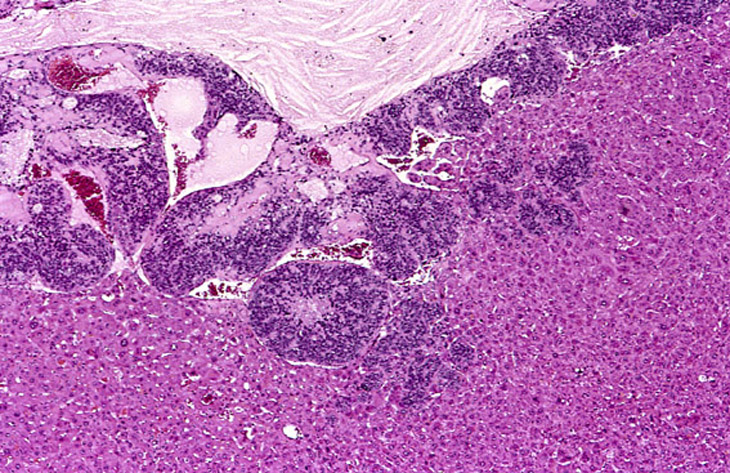

A large hepatoblastoma; higher magnification shows malignant cells palisading around vascular structures.